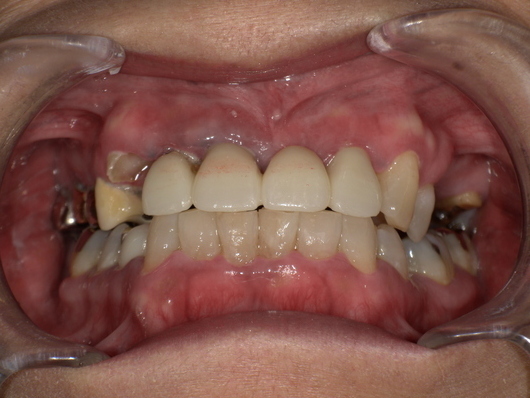

歯の詰め物(金属・銀歯)や薬剤の影響

古い銀歯や金属製クラウンから金属イオンが溶出し、口腔粘膜との接触でアレルギー反応が生じる場合があります。クロム・ニッケル・金・水銀などが原因物質となることがあり、金属アレルギーのある人は特に注意が必要です。